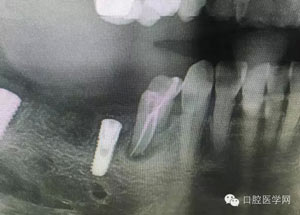

病例1:患者迫切希望保留自己的這一顆牙齒,根尖周陰影比較大,二度松動.而且旁邊有種植修復(fù)體,和患者溝通好后,治療好后觀察一個月后冠修復(fù),因為有種植的后期修復(fù),所以有了機會觀察,術(shù)后三個月和術(shù)后四個月,根尖恢復(fù)的還算不錯,希望能夠繼續(xù)觀察下去.這樣子的病例,做的時候我們一定要非常的小心,和患者要有充分的溝通以及不同科室的溝通然后決定怎么樣做比較好,假如就是出現(xiàn)了問題,到時候我們也比較好處理些,免得我們自己到時候不好收場。